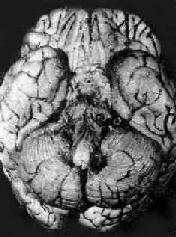

病理变化以脑底最明显。在脑桥、脚间池、视神经交叉及大脑外侧裂等处之蛛网膜下腔内,有多量灰黄色混浊胶冻样渗出物积聚。偶见比粟粒还小的灰白色结核结节(图18-14)。脑室脉络丛及室管膜有时也可有结核结节形成。镜下,蛛网膜下腔内炎性渗出物主要由浆液、纤维素、巨噬细胞、淋巴细胞组成,常有干酪样坏死,偶见典型结核结节形成。病变严重者可累及脑皮质而引起脑膜脑炎。病程较长则可发生闭塞性血管内膜炎,从而可引起多发性脑软化。未经适当治疗致病程迁延的病例,由于蛛网膜下腔渗出物的机化而发生蛛网膜粘连,可使第四脑室上中孔和外侧孔堵塞,引起脑积水。

结核性脑膜炎

图18-14 结核性脑膜炎

脑基底部脑膜增厚,有散在的结核结节